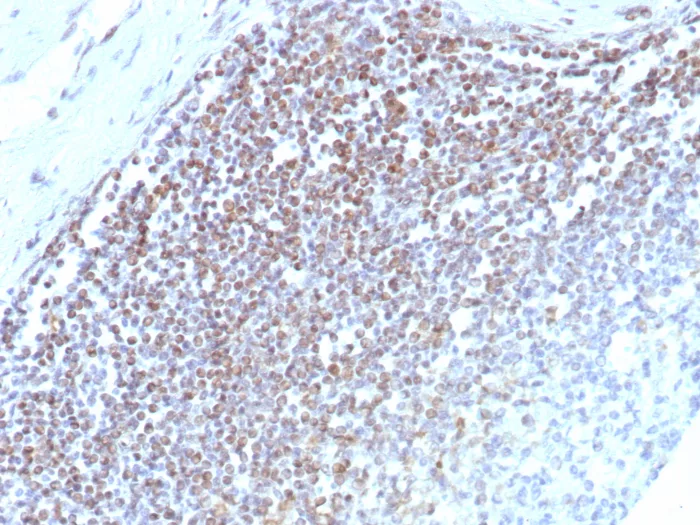

Formalin-fixed, paraffin-embedded human tonsil stained with E2F4 Recombinant Rabbit Monoclonal Antibody (E2F4/8984R). Inset: PBS instead of primary antibody; secondary only negative control.